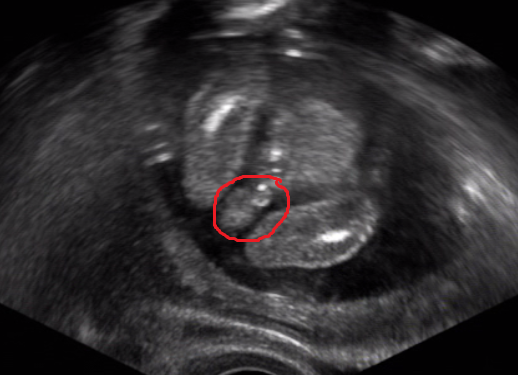

Ahoj kočkyyy, pardon že vás tak zanedbávám, ale mám toho moooc. Klári moc mě mrzí, že si zase v nemocnici, tak hodně odpočívej ať se ta mrška zase zmenší a ty můžeš domů. Jinak ve čtvrtek jsem byla na utz a nádherně se nám ukáza - máme chlapečka :-) moc jsme si přáli chlapečka, přítel je uplně nadšený. Je to naše první dítko. Testy z I. screeningu dopadly dobře :-) Malý má už 12 cm, a už tam byl celý takový skrčený. Navíc jsem ve středu cítila poprvé pohyby. večer celá ulítaná jak se vše sklidnilo jsem si masírovala bříško a najednou to přišlo, bylo to boží :-) Dostala jsem žádanku na velký ultrazvuk, na který se mám objednat. Tak vám držím pěstičky a´t je taky vše v pořádku

Jinak tady má malý krásné selfiičko